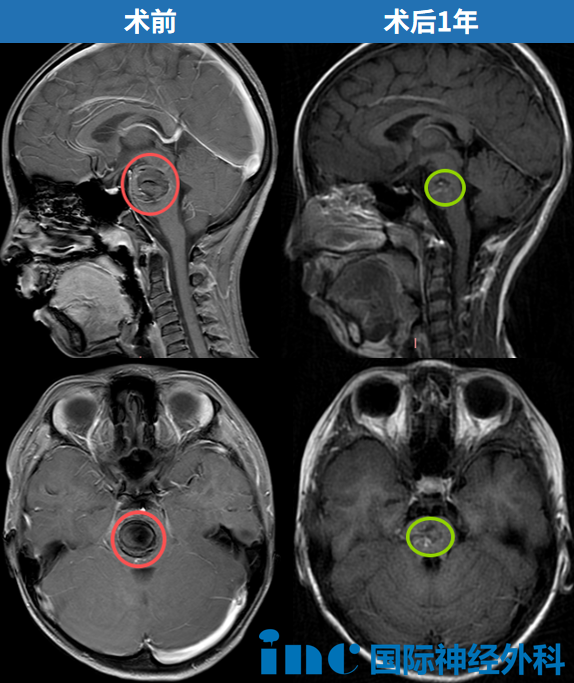

术后十六个月,得知巴教授再次来华,萌萌一家专程赶来当面致谢。巴教授复查了萌萌的最新影像,告诉她们:恢复情况非常好。